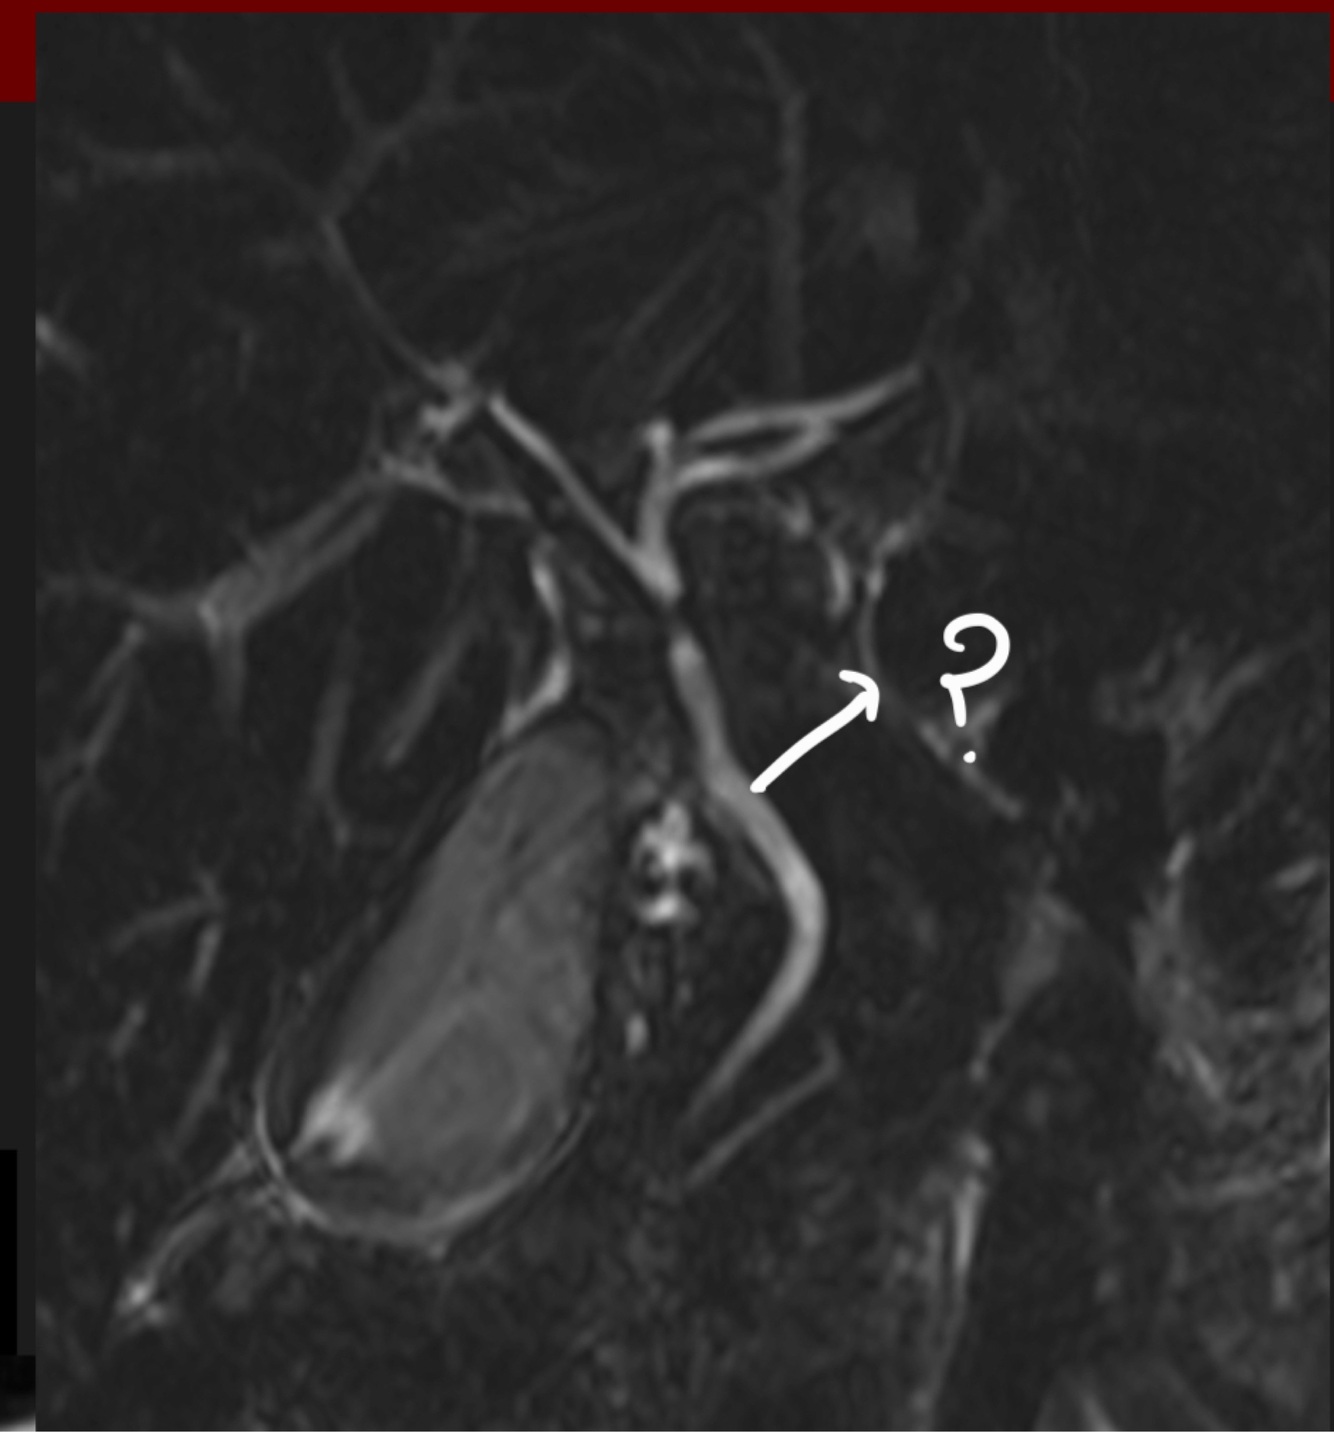

Q

What kind of image and structure

A

MRI T2, bile duct.

It is seen so clear because of the bile, which is a fluid and is very well seen in MRI T2.